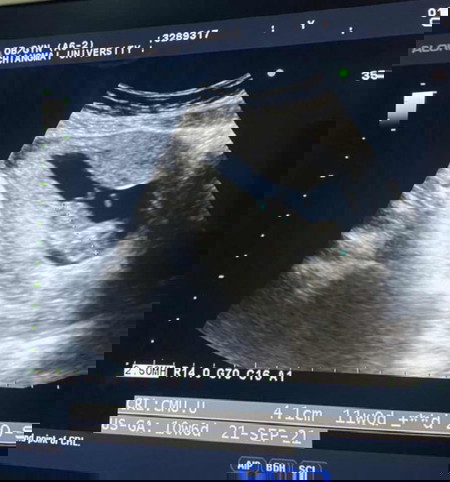

อัลต้าซาวดูครรภ์ 11 week ปรากฎเจอเนื้องอกในมดลูก 4 เซน จะเป็นอันตรายต่อแม่และลูกไหมค่ะ ช่วยแนะนำหน่อยคะ